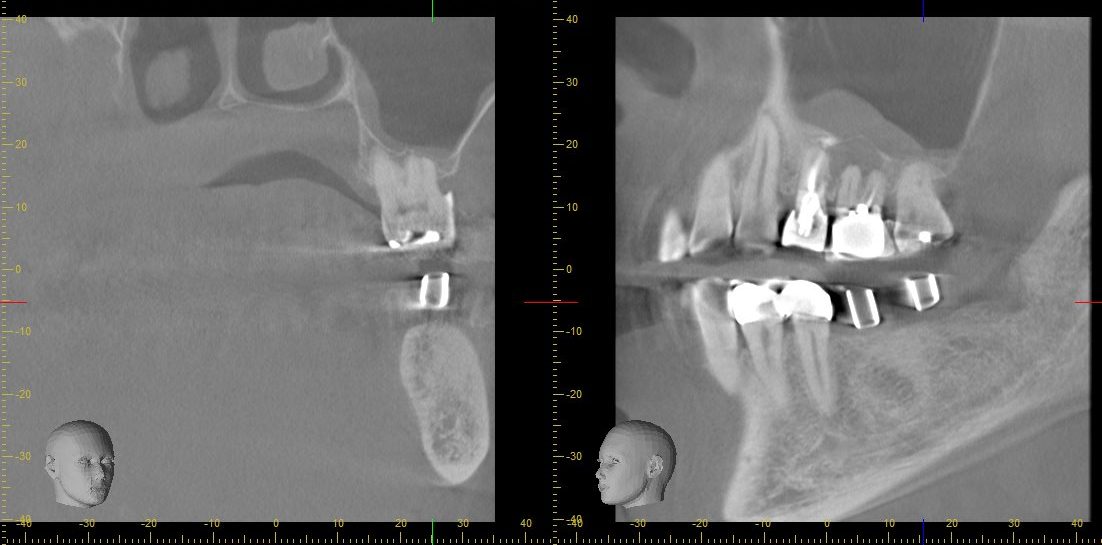

歯を支える顎の骨の密度や状態を確認することで、骨粗鬆症の可能性やインプラント治療の適応を評価できます。

術前のCT画像によるインプラントシミュレーション。骨幅・骨高・重要な解剖学的構造(上顎洞、下歯槽管)を立体的に評価しています。